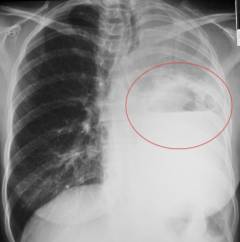

Поражение легких

Саркома легкого – редкое заболевание, составляющее около 1% случаев рака легких. На ранних стадиях оно часто не проявляется и выявляется случайно при рентгеновском обследовании.

Саркома формируется из стенок бронхов и перегородок между альвеолами. Опухоль содержит немного соединительной ткани, имеет мягкую, желеобразную консистенцию с участками некроза. Она выглядит как массивный узел с размытыми границами и может занимать всю долю легкого, пронизанная множеством сосудов.

- Рентгенография. На снимке опухоль видна без четких границ, размеры варьируются от нескольких сантиметров до объема целого легкого. Поражение легких не симметрично.

- Компьютерная томография позволяет выявить неоднородное округлое образование с размытыми краями и участками некроза. Узел не имеет оболочки и прорастает в окружающие ткани. Злокачественные клетки часто располагаются вдоль бронха в виде пласта.